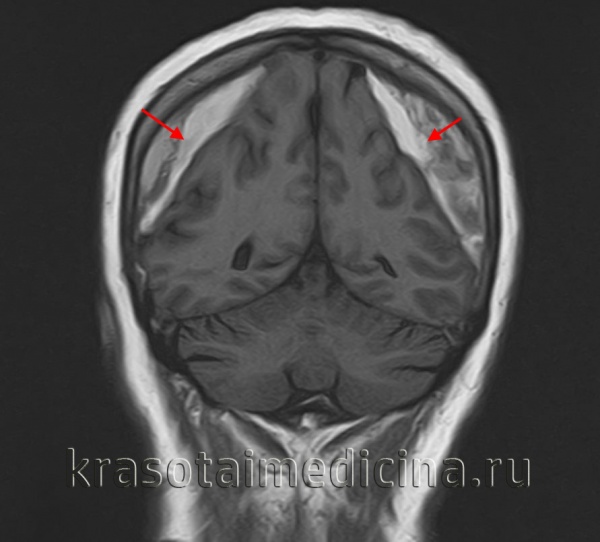

МРТ головного мозга. Массивная двухсторонняя хроническая субдуральная гематома.

Ключевыми методами диагностики субдуральной гематомы являются КТ и МРТ головного мозга. Для острых гематом предпочтительнее КТ, которая показывает однородную зону повышенной плотности серповидной формы. Со временем гематома разуплотняется, и через 1-6 недель она перестает отличаться по плотности от окружающих тканей. В таких случаях диагноз основывается на смещении латеральных отделов мозга в медиальном направлении и признаках сдавления бокового желудочка.

При МРТ может наблюдаться пониженная контрастность зоны острой гематомы, тогда как хронические субдуральные гематомы обычно имеют гиперинтенсивность в Т2 режиме. В сложных случаях помогает МРТ с контрастированием: интенсивное накопление контраста капсулой гематомы позволяет дифференцировать ее от арахноидальной кисты или субдуральной гигромы.